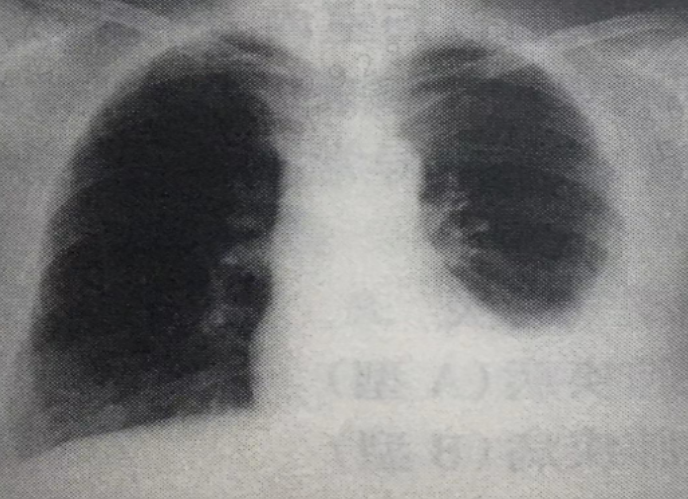

3、患者,男,53岁。胸闷、气短进行性加重1个月。既往糖尿病2年。胸部X线片如图所示。胸腔积液引流液草绿色,生化检查示:血清总蛋白(TP)45g/L,乳酸脱氢酶(LDH)220IU/L,腺苷脱氢酶(ADA)45IU/L;有核细胞计数1000/mm3,单核细胞百分比90%。该患者最可能的诊断为()

A.肺炎旁胸腔积液 B.结核性胸膜炎 C.癌性胸腔积液 D.心功能不全 E.乳糜胸

患者胸腔积液的生化检查提示为渗出液,按照Light标准(LDH大于正常参考值的2/3),

常规提示有核细胞数不高,单核细胞为主。ADA>45IU/dl,符合结核性胸腔积液的

特点。